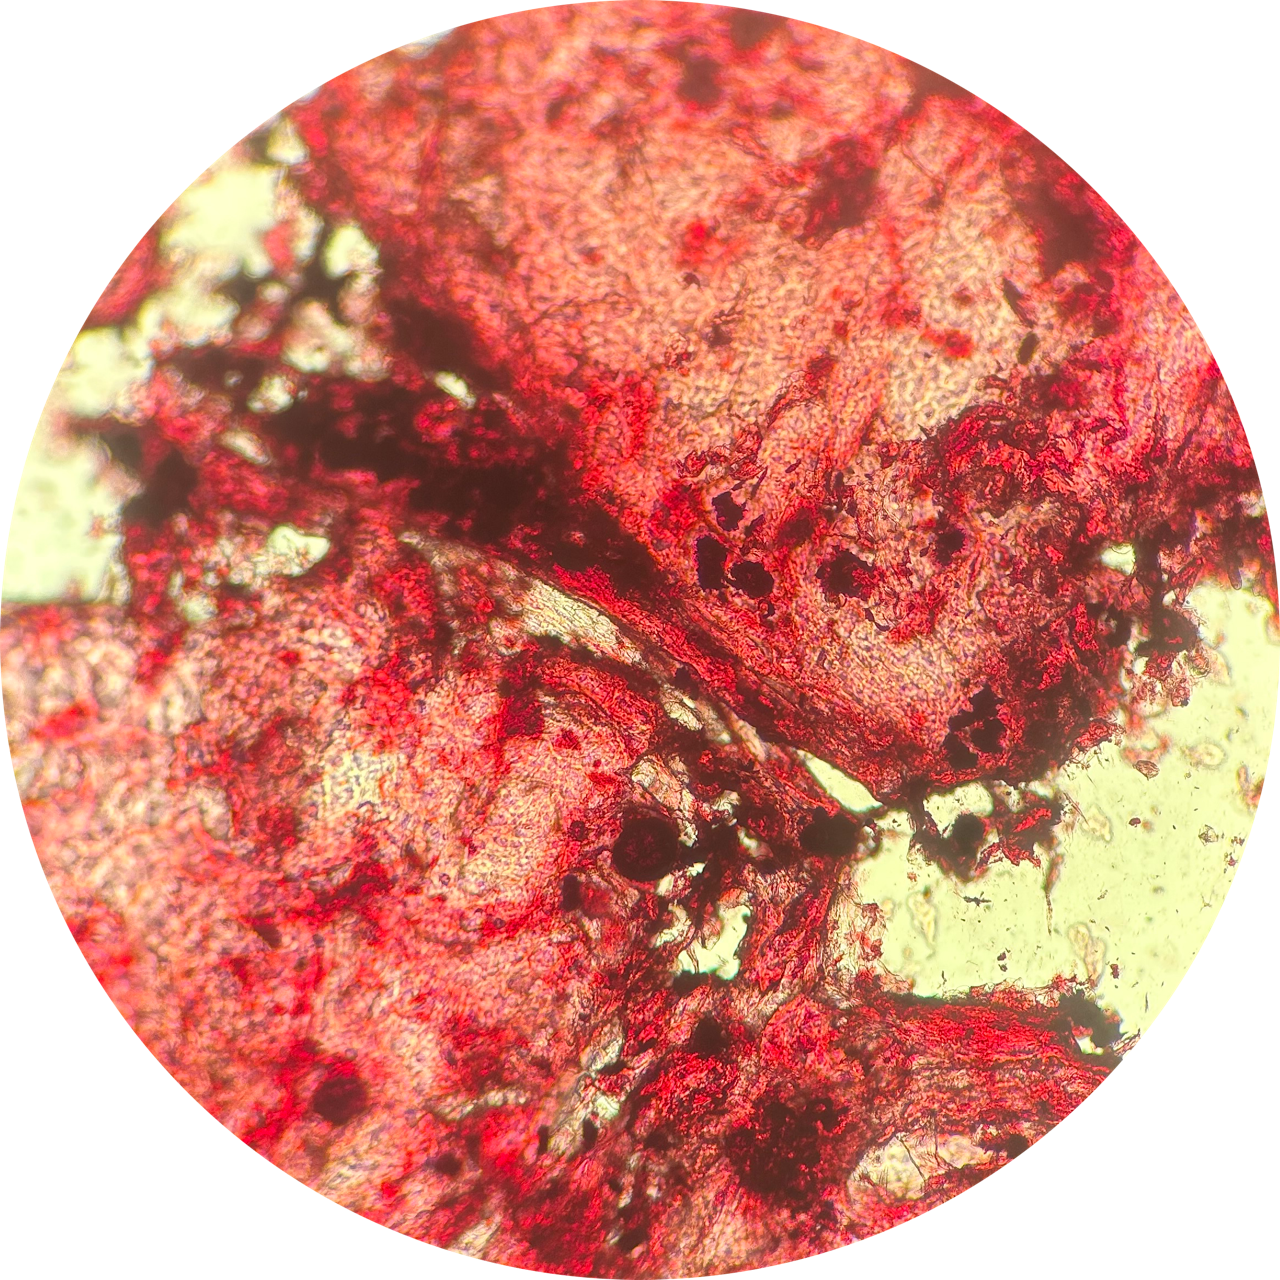

Microscope Slide, Cheek Scrapping, Fuchsin Cell Stain, Compound Microscope

This is a microscope slide I prepared myself from our Life Studies lab. I have an anxious habit known as Morsicatio buccarum, or chronic cheek biting, which leaves me with dead skin buildup and scar tissue on the inside of my mouth. This habit is a body-focused repetitive behaviour (BFRB) that can be associated with many different neurodiversities and psychological disorders, such as Autism, Anxiety, and Obsessive Compulsive Disorder (OCD), to name a few.

“The stress of my final year has caused an increase in anxious habits, so I felt it was intriguing to explore the physical manifestations of my anxiety under the compound microscope.”

Cheek Swab at 400x Magnification